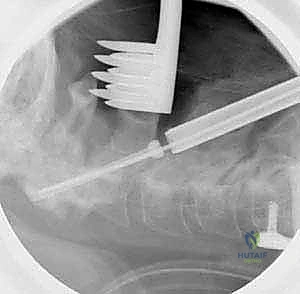

الخطوة 7: التصوير الشعاعي داخل العمليات

طوال الإجراء، وخاصة بعد تركيب المسامير والقضبان، يتم استخدام جهاز الأشعة السينية المحمول (C-arm